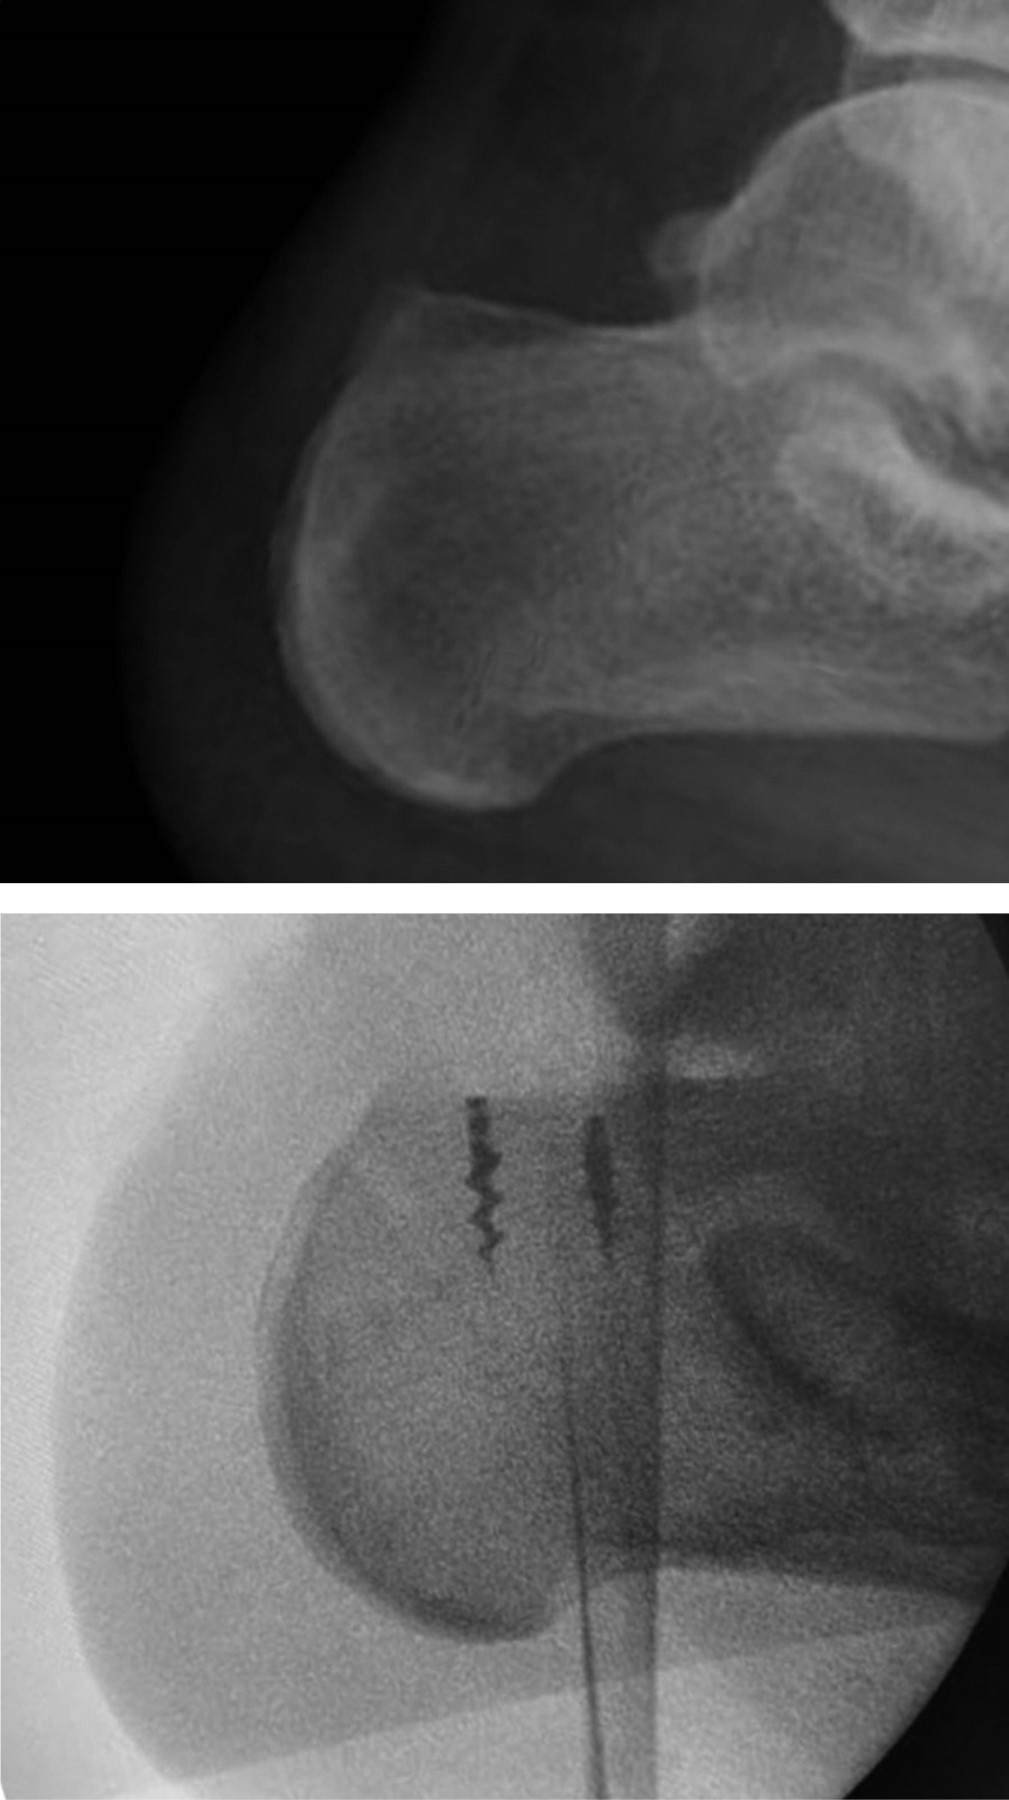

En nuestra primera consulta se envió a terapia física y rehabilitación realizando un total de ocho sesiones dentro de nuestra institución, no mostrando mejoría ni disminución del dolor, por lo que se solicitaron estudios de imagen, los cuales consistieron en radiografía anteroposterior y lateral de tobillo en la cual se evidenció adecuada congruencia de la articulación tibioastragalina y tibioperonea, exostosis posterosuperior de calcáneo de 6 milímetros de altura con relación a la línea articular superior, y alteraciones en la grasa de Kager (Figuras 1 y 2). De igual manera, se realizó resonancia magnética de tobillo evidenciando tendinitis aquílea, bursitis retrocalcánea y líquido en la bursa retroaquílea de aproximadamente 3 cm3. Se observa tendón aquíleo engrosado en su inserción y tendinitis insercional con edema óseo en región posterior de calcáneo (Figura 3).

Figura 1

Figura 2